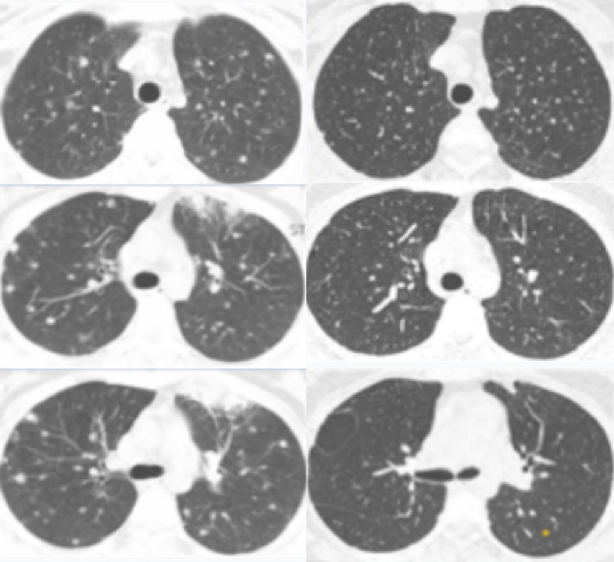

High resolution CT (HRCT) scan showed multiple peri-centimetric bilateral well defined parenchymal nodules predominantly peripheral and four areas of parenchymal densification with air bronchogram. A few mediastinal lymph nodes were observed although without dimensional criteria to be considered adenopathy (figure 2 left).

Figure 2 HRCT at presentation showing multiple peri-centimetric bilateral well defined parenchymal nodules predominantly peripheral and four areas of parenchymal densification with air bronchogram. Right HRCT scan more than a year later demonstrating a reduction of the earlier lesions (left) with some residual fibrotic changes.

At follow-up, spirometry and diffusing capacity remained normal as well as blood chemistry and angiotensin converting enzyme. A chest roentgenogram performed one year later showed a reduction of the interstitial features (figure 1B). High resolution CT revealed residual fibrotic changes at the sites where previously the bigger nodules had been (figure 2 right).